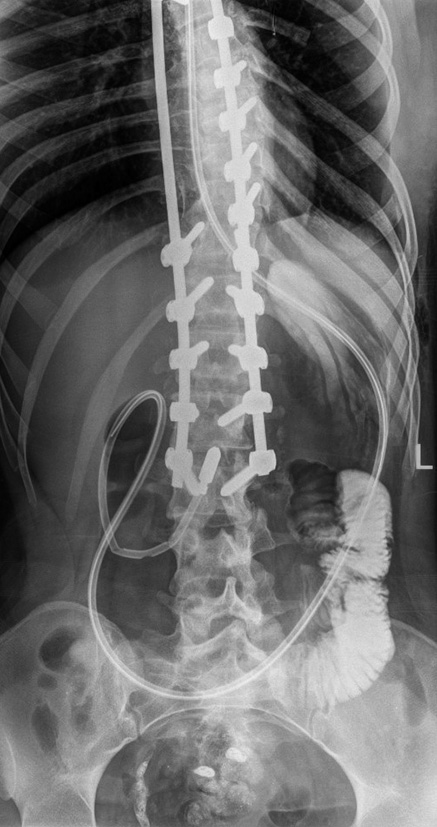

After a twofold change in body position (left side — back), a repeated X-ray control was performed (Fig. 5), which revealed the spread of the contrast agent into the jejunum. The introduction of the mixture into the duodenal probe was resumed. The mixture was absorbed completely without retrograde ingestion in the stomach.

Fig. 5. Repeated X-ray of the abdominal organs